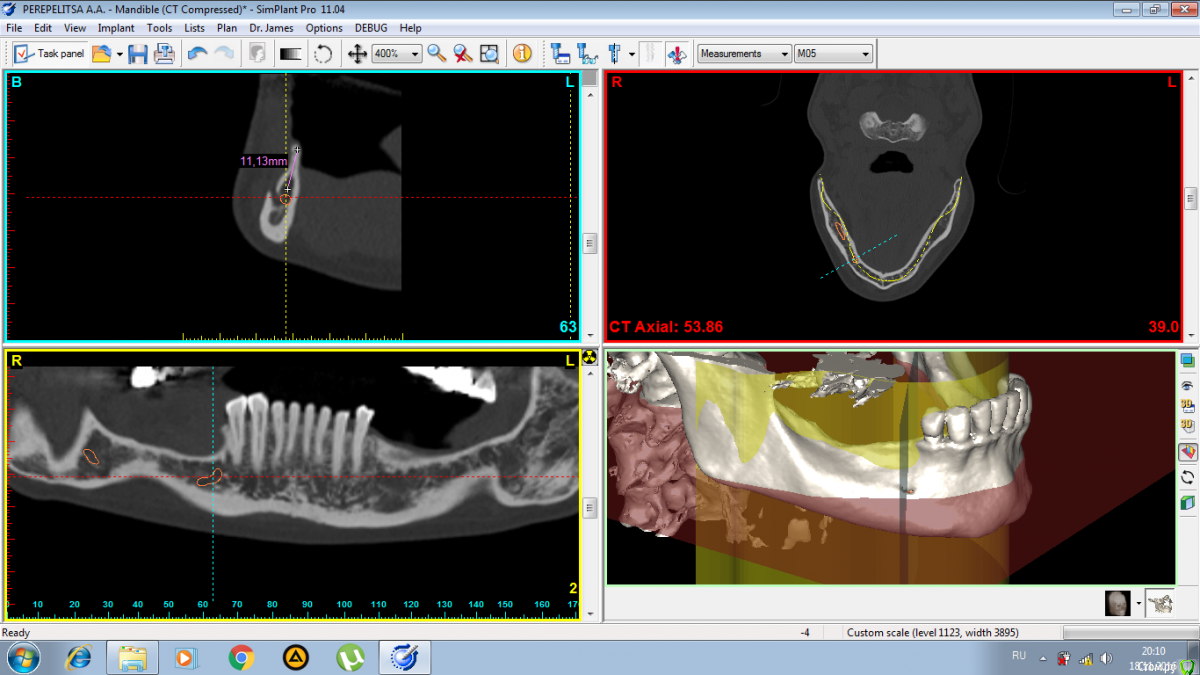

Makalester Опубликовано 27 ноября, 2016 Поделиться Опубликовано 27 ноября, 2016 Друзья, подскажите как лучше поступить в данном случае? Ламина, цитопласт, коллагеновая мембрана? Смущает тонкий монокортикальный гребень, выживет ли под ним что нибудь. Ссылка на комментарий

Makalester Опубликовано 28 ноября, 2016 Автор Поделиться Опубликовано 28 ноября, 2016 а какими методиками владеете? Здесь цитопласт или "кюри" Кюри не делал. Жесткие каркасы каркасы 50/50 , то нормально все, то оголится. Последнее время все больше сосидж 50ауто- 20 алло- 30 ксено, но тут смущает что питания мало((. Вот думаю если ламину или остеогвард, они резорбируются дольше чем биогайд и эволюшн? Ссылка на комментарий